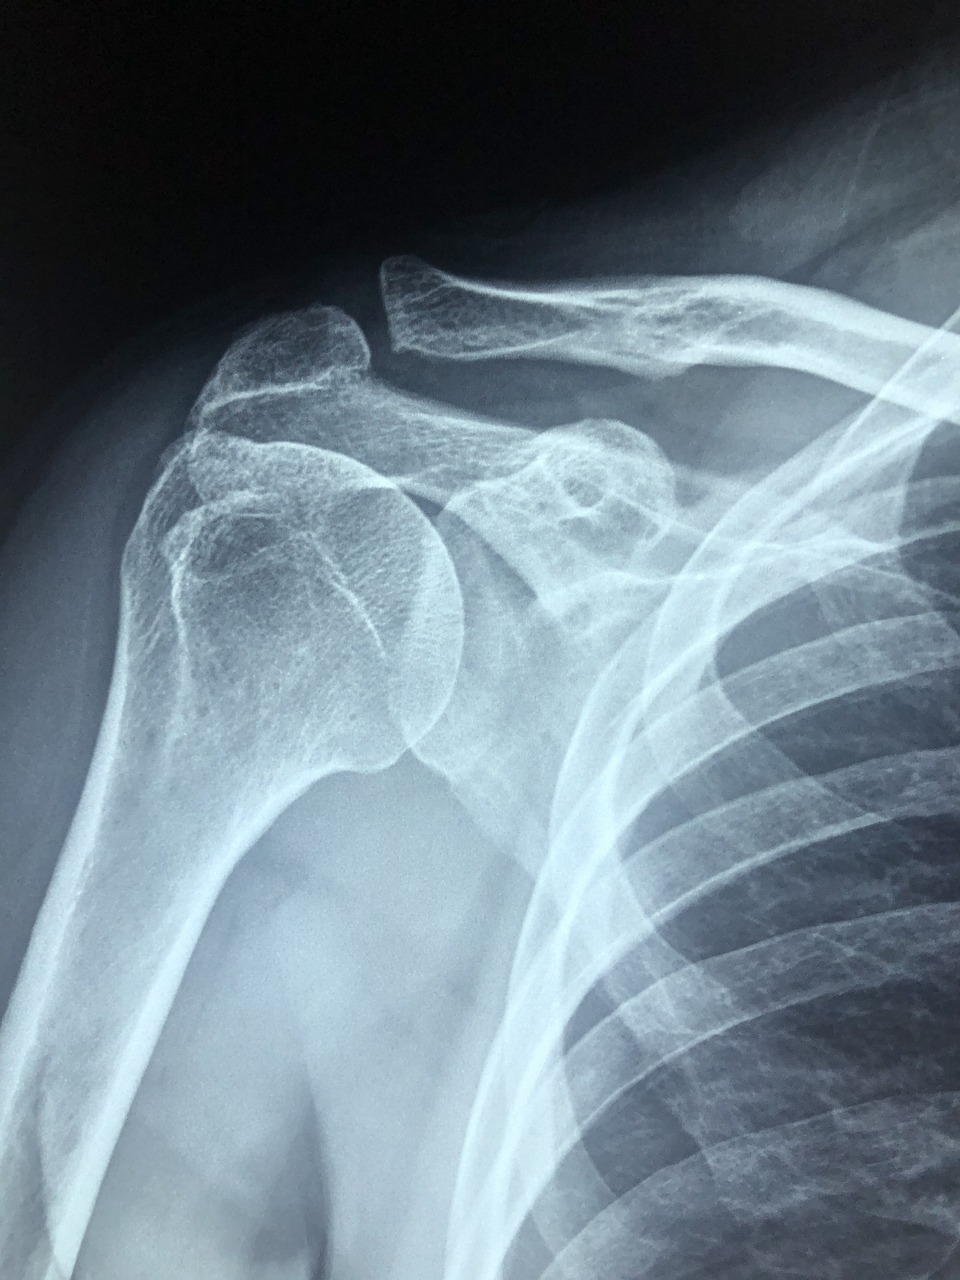

오십견은 흔히 50대 중장년층에서 자주 나타나는 질병으로 알려져있습니다. 정확한 병명은 '동결건' 이라는 질병인데요, 오십견 즉 동결건은 특별한 외상 없이 어깨 통증이 발생하고 그 통증으로 어깨 움직임에 지장이 생기는 질환을 의미합니다. 지금부터 오십견 증상 2가지로 정리해 소개해드리겠습니다.

- 심한 통증 및 야간 통증 : 가장 큰 특징으로 어깨에 발생하는 심한 통증이며 주로 야간에 어깨에 굉장한 통증이 옵니다. 저희 아버지의 경우엔 잠을 제대로 이루지 못하실정도로 고생하셨는데요, 이유없이 어깨에 심한 통증이 온다면 오십견의 증상 중 하나로 볼 수 있습니다.

- 어깨 관절 운동 제한 : 가장 처음으로 나타나는 증상은 어깨를 안쪽으로 돌리기 힘들어지는 것입니다. 어깨 다음으론 팔을 앞으로 들거나 밖으로 돌리기 힘들어집니다. 가령 세수나 머리를 감을 때 목을 만지는 행동, 머리를 빗을 때, 셔츠 단추를 끼우는 행동을 하기 어렵습니다.

결론은 어깨에 매우 심한 통증과 함께 어깨 관절 운동이 제한된다는 점 입니다. 오십견의 증상을 알아보았다면 내가 오십견인지 알아볼 수 있는 자가진단법을 소개해드리겠습니다.